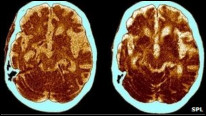

Picha ya Kopyuta ikionyesha athari za Alzheimer

Vipande vya protini, kwa lugha ya kitaalamu (plaques) au utando kwenye ubongo yanadhaniwa kuwa sehemu nyeti inayosababisha maradhi haya.

Utando kwenye ubongo